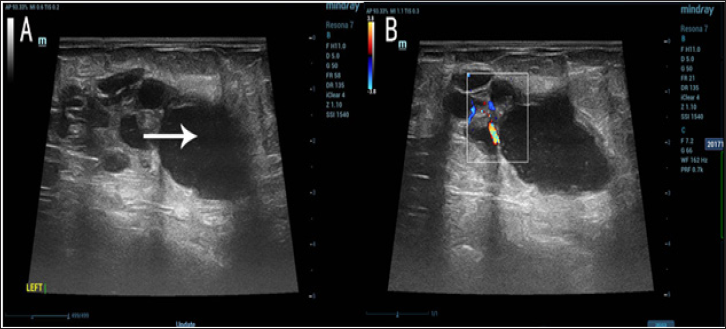

3. Problemas vasculares

Las tomografías también pueden revelar problemas en los vasos sanguíneos, como aneurismas o coágulos de sangre. Estos hallazgos pueden ser críticos, especialmente cuando se sospecha que hay una interrupción en el flujo sanguíneo o riesgo de un evento vascular, como un derrame cerebral o un infarto. Las tomografías con contraste, en particular, son útiles para visualizar las arterias y venas y detectar posibles bloqueos o dilataciones.

Las tomografías también pueden revelar problemas en los vasos sanguíneos, como aneurismas o coágulos de sangre. Estos hallazgos pueden ser críticos, especialmente cuando se sospecha que hay una interrupción en el flujo sanguíneo o riesgo de un evento vascular, como un derrame cerebral o un infarto. Las tomografías con contraste, en particular, son útiles para visualizar las arterias y venas y detectar posibles bloqueos o dilataciones.

6. Problemas abdominales

La tomografía abdominal es fundamental para identificar afecciones como cálculos renales, enfermedades del hígado, apendicitis y trastornos digestivos. La TC permite observar el abdomen en detalle, destacando problemas en los órganos internos y ofreciendo información sobre el tamaño, la forma y la función de estos órganos.

Varios factores pueden influir en la calidad y la precisión de los resultados de una tomografía. Uno de los principales es el uso de contraste en la tomografía. El contraste, que generalmente se administra por vía intravenosa, ayuda a resaltar ciertas áreas del cuerpo, como los vasos sanguíneos y los órganos internos. Sin embargo, no todos los pacientes pueden ser aptos para este tipo de procedimiento, especialmente aquellos con problemas renales o reacciones alérgicas al contraste.